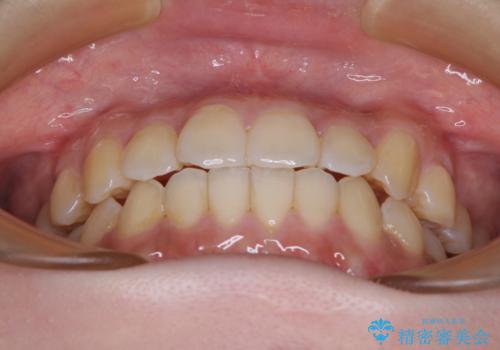

舌側転位している側切歯特有の、切縁の位置が不揃いであったり、根元が内側に引っ込んだ状態であったりという、インビザライン独特の仕上がりになることなく、きれいに整った歯列とすることができました。